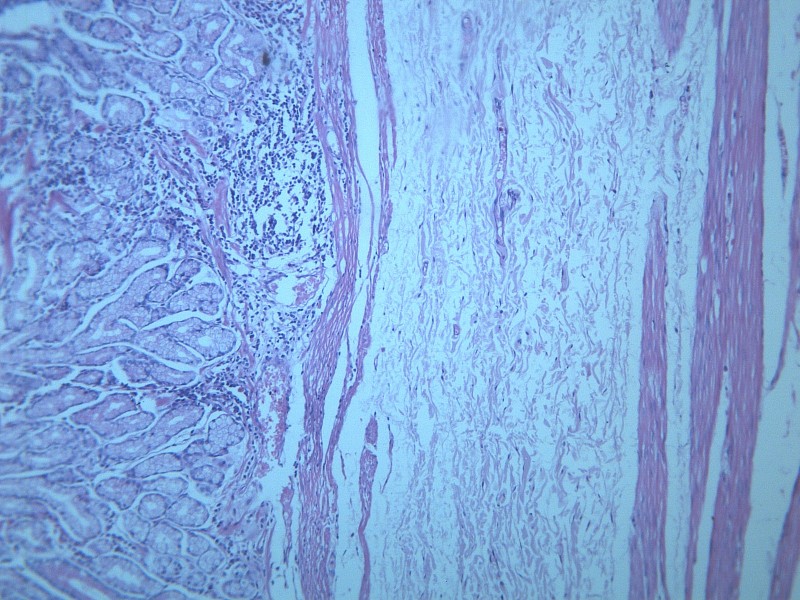

慢性萎缩性胃炎 显微切片图片(18张)

本病以胃粘膜萎缩变薄,粘膜腺体减少或消失,并伴有肠上皮化生,固有膜内多量淋巴细胞、浆细胞浸润为特点。本性胃炎的病因比较复杂,部分可能与吸烟酗酒和用药不量有关,部分由慢性浅表性胃炎迁移发展而来,还有部分属兔自身免疫疾病。